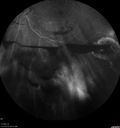

PDR and Vitreous Hemorrhage - High Risk Left Eye - Low Risk Right Eye369 views50 year old man with type I diabetes mellitus for 26 years. New Vitreous Hemorrhage in the left eye. Both eyes have NVE. Both also have foveal hypoplasiaMar 07, 2020